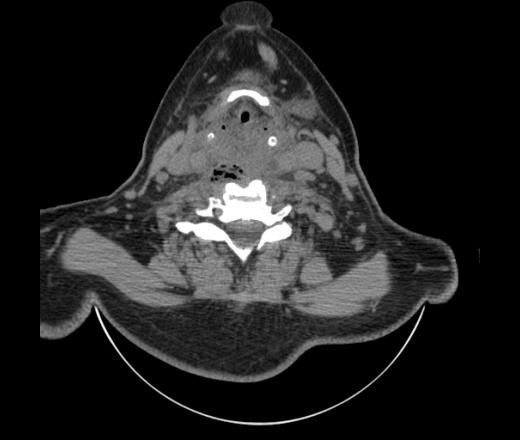

Женщина поступила в х/о спустя 4 дня после того как при употреблении карася подавилась костью.

Наличие газа в средостении на протяжении тел С2-С6 (медиастинальна эмфизема); рыбная кость на уровне тела С6.

При всем уважении, но говорить о медиастинальной эмфиземе, оценивая мягкие ткани шеи, как-то слишком резко. На мой взгляд, это ретрофарингеальное пространство.

Эвакуировали почти 100мл гноя. Но кость не смогли найти. Думаю что она даст дальнейшее ослоднение. Эндоскопически за черпалонадгортаной звязкой не смогли зайти в пищевод, все мягкие ткани отечные, просвет пищевода сдавлен. По всей видимости параэзофагеальная клетчака тоже задействована. Эмпиема, если ее можно так назвать, незнаю как правильно дошла до уровня яремной вырезки. Чем закончиться напишу. Ждем медиастинита.

Согласен с Вами; конечно, наличие газа в клетчатке ретрофарингеального пространства (затмение с опечаткой..). К сожалению, процесс "продвигается" к медиастиниту. Но почему никто, не отмечает наличие рыб. кости; или это для Всех очевидно?

Кость то мы сразу выявили, размеры где то 17*2мм, но ее так и не получается найти в этой каше